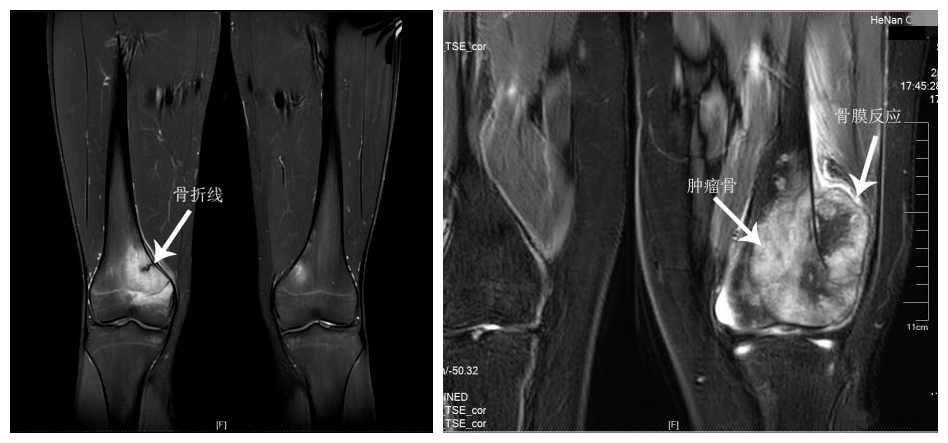

发现典型的骨折线,恶性骨肿瘤存在诸如皮质骨破坏,瘤骨形成,"codman三

云絮状瘤骨,骨膜反应和codman三角,软组织肿块分类:成骨型,溶骨型